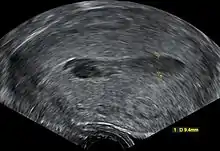

يتم تشخيص تدمي الرحم عن طريق أخذ التاريخ المرضي للمريضة؛ إذ تعاني من انقطاع الطمث و ألم دوري في البطن، وبجس الحوض نجده صلباً وأكبر حجماً.[4] و يتم التأكد عن طريق أشعة الرنين المغناطيسي إذ يظهر الرحم أكبر حجماً وممتلئاً بالدم[4][5]، و يساعد تنظير البطن في تشخيص العيب الخلقي التي قد تسبب تدمي الرحم إن وجد.[2]